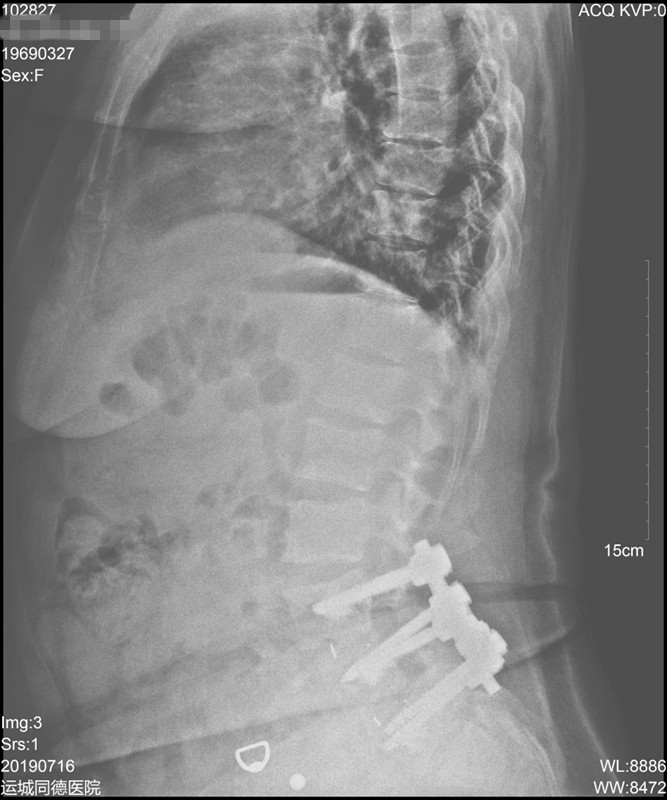

辅助检查:我院全身ECT骨显像+断层:双侧多根肋骨、第7、8、10、11、12胸椎、第1腰椎、左侧耻骨支、坐骨支、耻骨联合、双侧肩关节、肘关节、腕关节、骶髂关节、髋关节、踝关节可见多处放射性浓聚CT定位相可见多处肋骨、肋软骨连接处假骨折。胸腰椎正侧位片示:胸腰段骨质密度减低,骨皮质变薄或皮质线不连续,腰3-5椎体术后改变。骨盆前后位片示:左侧耻骨上下肢骨折,左股骨干上缘外侧皮质刀割样假骨折,右髋关节置换术后改变,腰椎内固定术后改变,右侧耻骨下支骨折。双髋关节CT示:左侧耻骨上下支骨折畸形愈合,右侧耻骨下支骨折,骶骨、左侧股骨颈陈旧骨折改变,右髋关节置换术后改变。曾行全身PET未发现肿瘤。

▼ 腰椎侧位片: